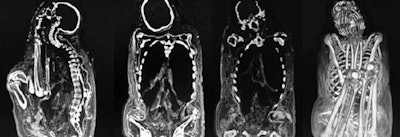

In Peru we have used x-rays for the study of mummies from the Paracas culture, a civilization that preceded the Incas and used to deform aristocratic babies' skulls. They also practiced cranial trepanation, one of the oldest surgical procedures for which there is archaeological evidence. CT and x-ray studies confirmed that some of the people who underwent the procedure survived the treatment, as both modalities showed signs of cicatrization, such as new growth and trepanation closure in skull bones.

Also, we need to know what mummification consists of and how it can be carried out: either in the artificial way as on Egyptian mummies, or mummification that occurs naturally depending on climatic conditions. In desert areas, organs dehydrate and dry up, and at high altitudes such as in the Andes Mountains, organs freeze with low temperatures. Extreme cold does not dry up organs, but it creates fat saponification, a process that leaves the organs almost intact.